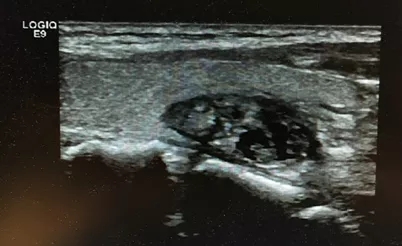

图1 甲状腺良性结节消融前纵切位 30×22×20mm

图2 甲状腺良性结节消融前横切位 30×22×20mm

中年女性,45岁,发现左侧颈部包块1年余入院。

查体:左侧甲状腺可触及大小3cm左右包块,质地韧,可以随着吞咽上下活动,无明显压痛。

彩超:左侧甲状腺内可见大小30×22×20mm囊实性包块。

术前细胞学穿刺:见滤泡上皮细胞及多核巨细胞,细胞无明显异型性,良性甲状腺结节。